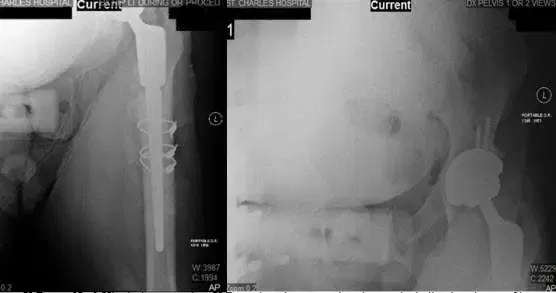

X-Ray of Bilateral Hip. X-ray shows Left THA along with new bone formation along the lateral and proximal shaft of the femur.

The patient had stated that he was feeling good relief from the pain medication. Upon examination, he was experiencing tenderness over the greater trochanter of both the lower left and lower right extremities. At subsequent follow-ups the X-rays reviewed were normal and showed that there was no acute displaced fracture and possible focal osteopenia of the loosening. The patient was advised to begin weight bearing as tolerated and continue Vitamin D3 5,000 IU daily.